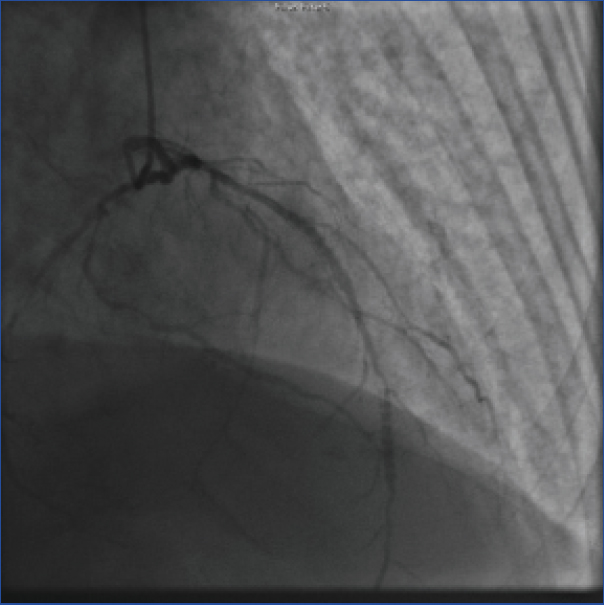

Angiography of coronary arteries showing narrowing of left anterior descending artery with 70% stenosis prior to the procedure.